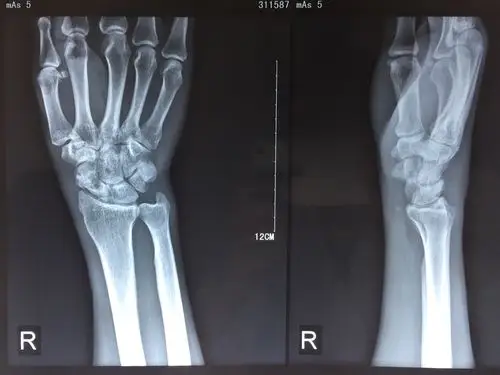

相关图片